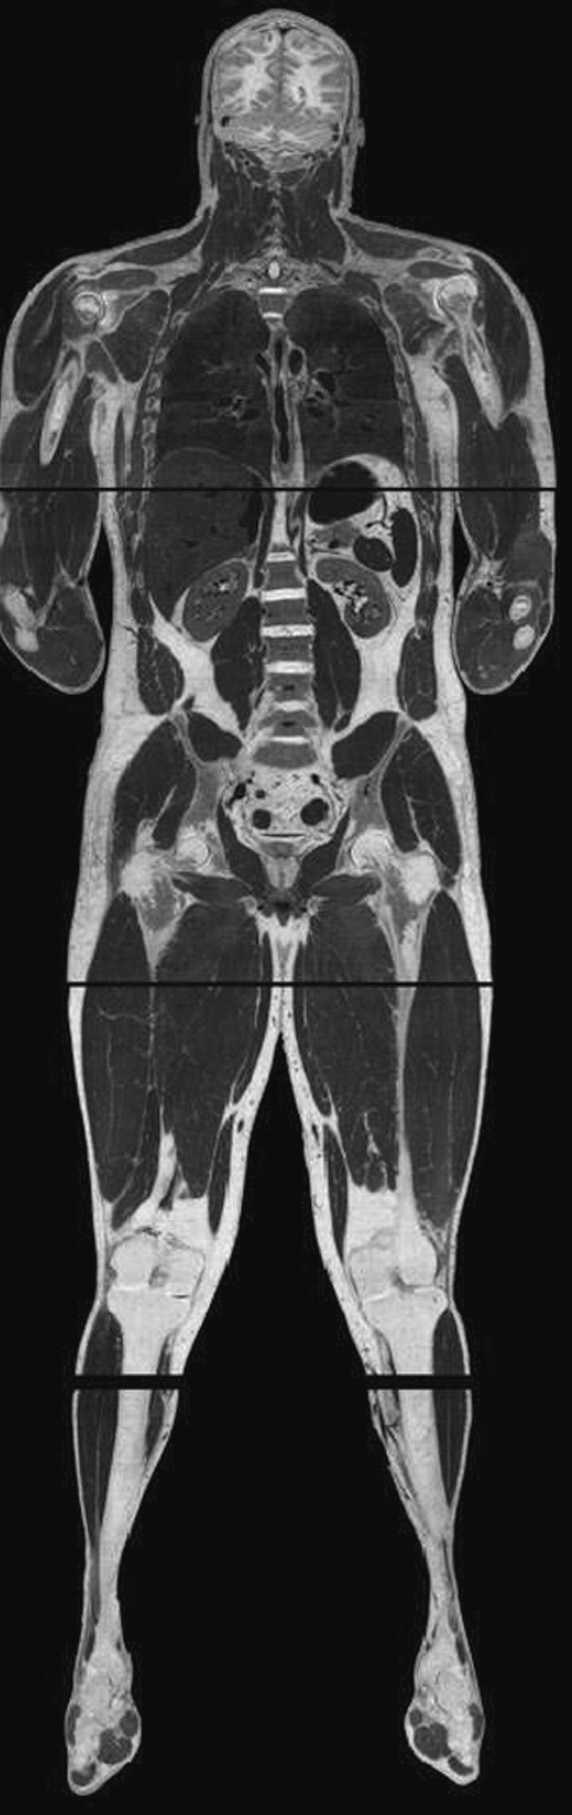

Modelización geométrica:la creación de modelos geométricos tridimensionales se suele basar en la utilización de imágenes médicas (tomografía computarizada, resonancia magnética, ecografía tridimensional, etc.). La creación en 1995 de la base de datos Visible Man por la biblioteca nacional de medicina de Estados Unidos (The Visible Human Project® Long-Range Plan NLM’s)15 ha permitido recrear un modelo de imágenes bastante completo del cuerpo humano (fig. 4). Sin embargo, la integración de algunas estructuras anatómicas en las imágenes médicas todavía necesita de investigación y trabajo manual debido a su baja resolución.

Fig. 4.Visible Man: modelo del cuerpo humano.